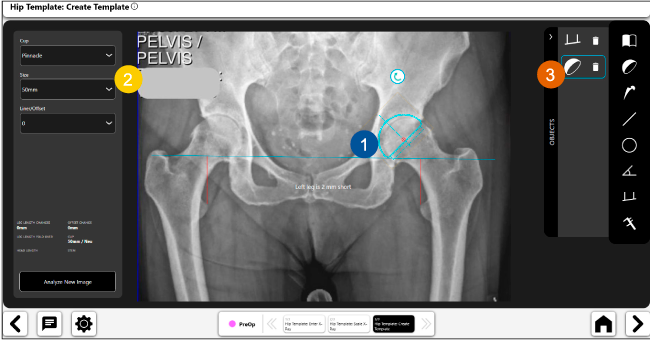

Planeación preoperatoria mediante la creación de plantillas digitales para reemplazo de cadera y análisis intraoperatorio

Beneficios de la planeación preoperatoria con Velys Hip Navigation ™

Disponibilidad de plantillas digitales de cadera.

Expediente histórico y personalizado, optimiza la planeación con el calendario de casos realizados en Velys TM y utiliza los íconos interactivos para una rápida revisión.